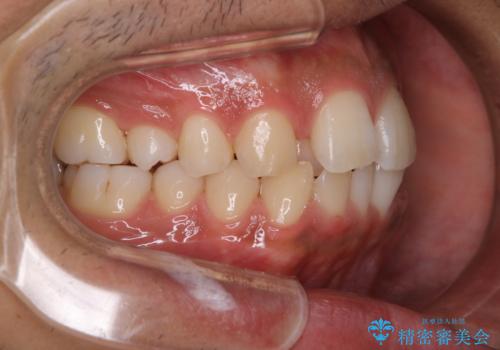

矯正をスタートする前にクリーニングを行いました。PMTC60分コースを行いました。

10年ぶりのクリーニングのため着色や歯石、プラークの量は多めでした。